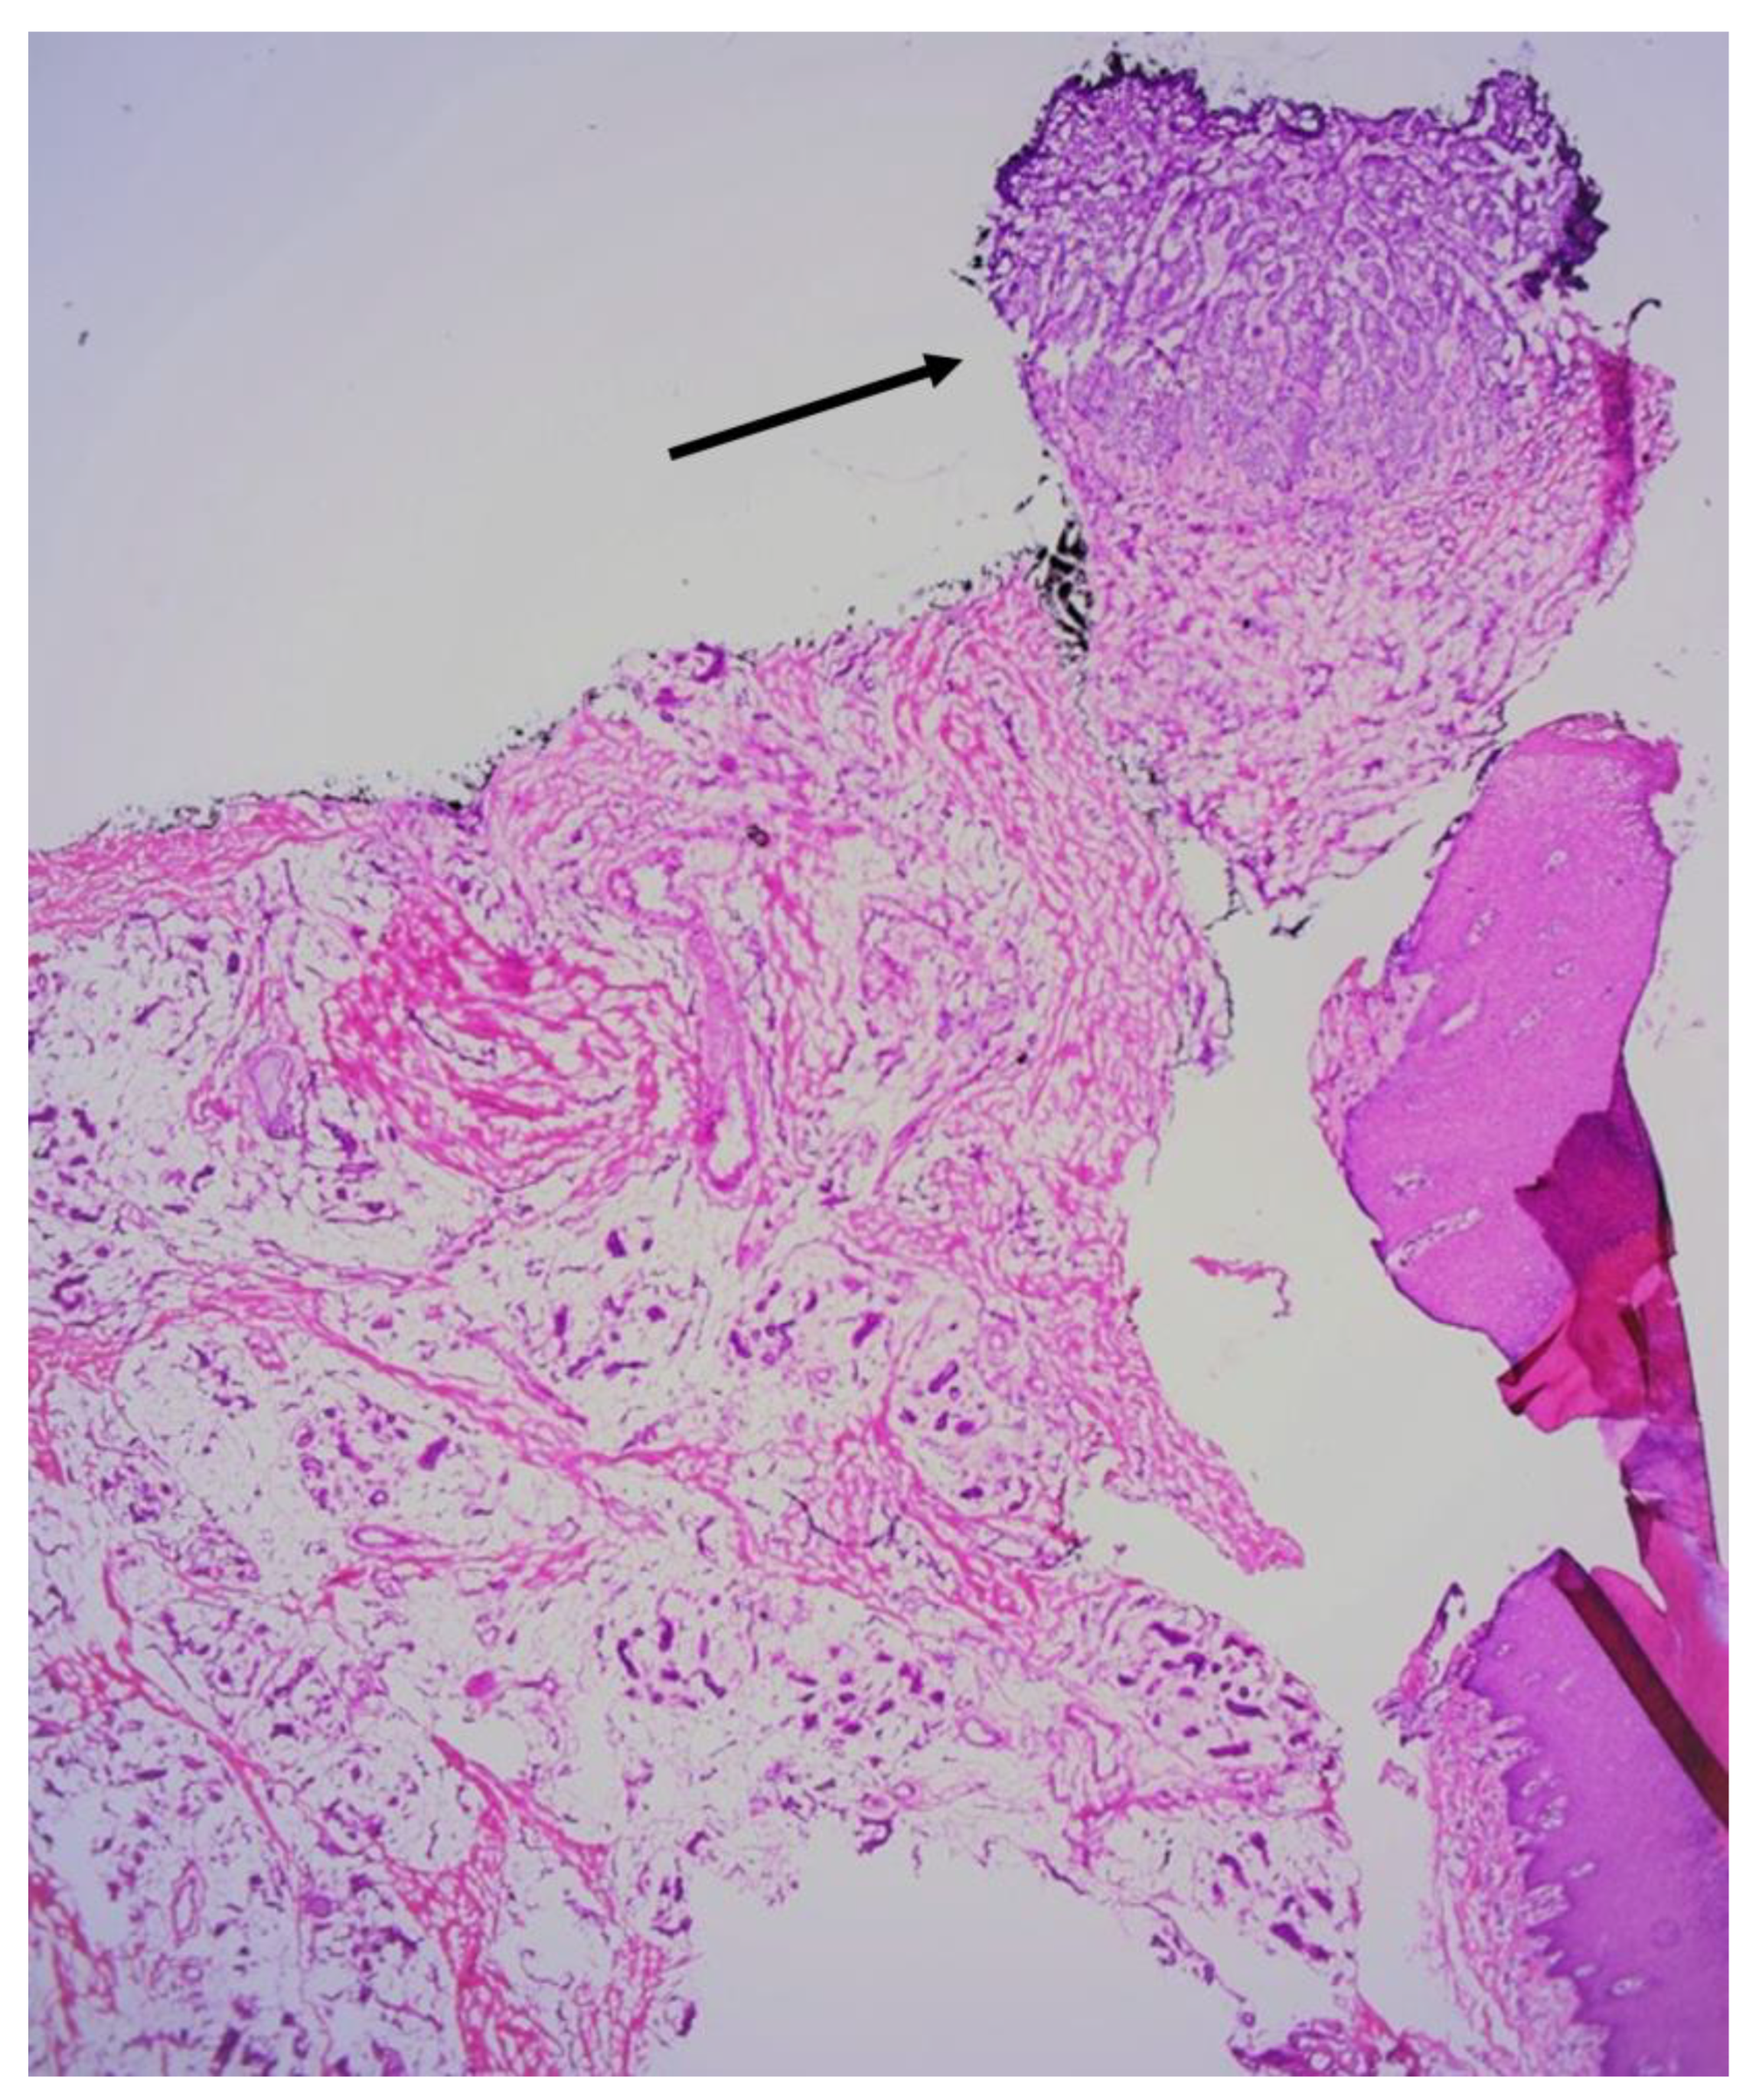

2. Case Reports

2.1. Patient 1

2.2. Patient 2